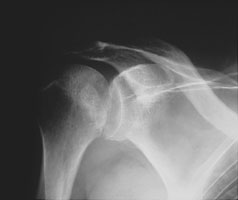

Posterior dislocations of the humerus account for less than 5 % of shoulder dislocations and are usually due to direct force. Classically, the causes are seizure or electric shock. The axillary view is the best view to demonstrate this type of dislocation.

- Click on the image for a larger versionBAxillary radiograph. Notice the anterior coracoid with the posteriorly dislocated humeral head relative to the glenoid.